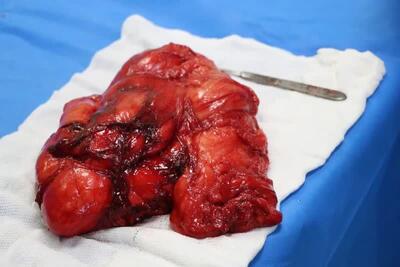

تومور 2کیلویی از بازوی بیمار بابلی خارج شد - تسنیم

عضو هیئت علمی دانشگاه علوم پزشکی بابل از خارج کردن تومور 2کیلویی از بازوی بیمار بابلی در بیمارستان آیت الله روحانی بابل خبر داد.